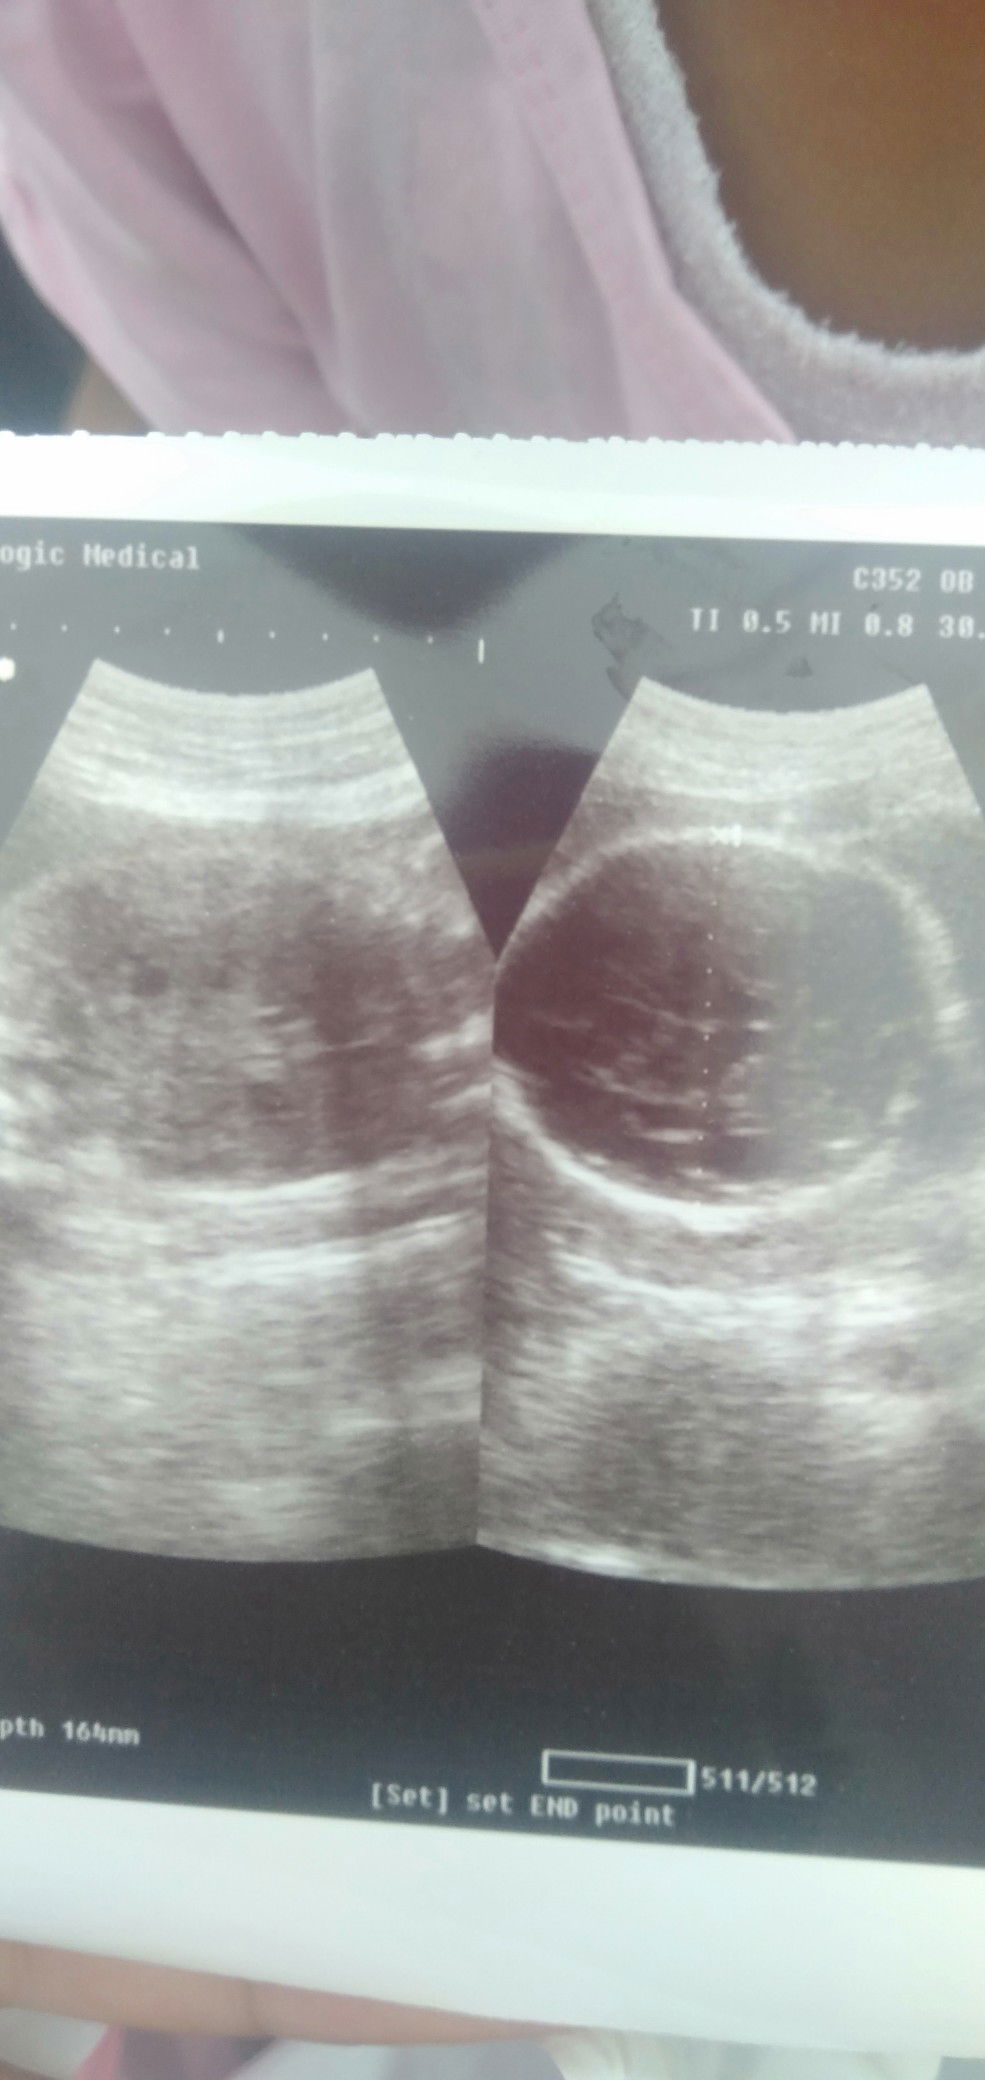

Bun saya ru aj USG Bun, ank saya sehat2 aj Bun. Tpi kta dokter ank saya berat ny 1,3 kg Bun kndugn sya msh jln 6 Bun. Jdi dokter blg jgn minum es ge Bu. Tpi saya klw gk minum es sya lemes Bun. Jdi saya harus gmna Bun???